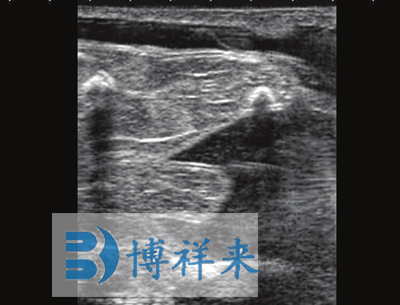

可换探头,可配备:128振元(5-8MHZ)直肠探头、128振元凸阵(2.5-5MHZ)直肠探头、128振元微凸探头以及特殊探头、支持3.5兆赫至7.5 MHz扇形探头等 支持用户可选择探头扫描方向 |